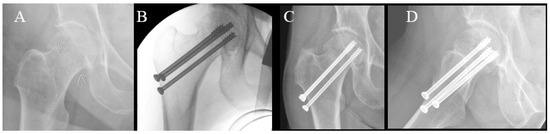

Figure 4.

Radiographs of cannulated hip screw fixation with two screws. (A) Preoperative radiograph. (B) Perioperative radiograph. (C) Anteroposterior radiograph at 6-week follow-up. (D) Lateral radiograph at 6-week follow-up.